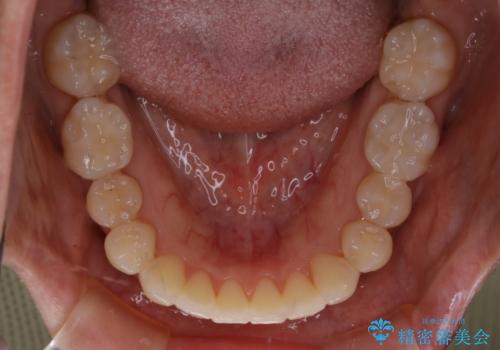

- 矯正治療が終了して歯並びが綺麗になると、元々入っていた銀歯が気になってきたとのことで適合の良いセラミックへのやり替えを行いました。

適合不良の補綴物は二次的な虫歯発生のリスクが高まります。

自費診療で用いられる材料は保険適応の材料に比べて、より精密で適合の良い被せ物作ることができるため、長期的な虫歯のリスクを大幅に減らすことが可能です。